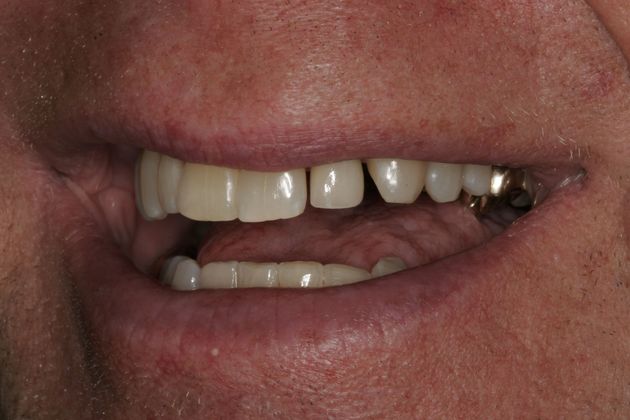

Cosmetic Dentistry Institute

Drs. David Whalen and Mariam Hanna in Troy, MI, have created a spa-like atmosphere where you can relax while receiving gentle dental care. Patients choose our team because of several distinctions

- We're one of the few offices in the world to have accredited members of the AACD

"Dr. Craig Goldin, Dr. Marcy Goldin and Dr. David Whalen have earned the privilege of being noted among the world’s best, most knowledgeable cosmetic dentistry experts."